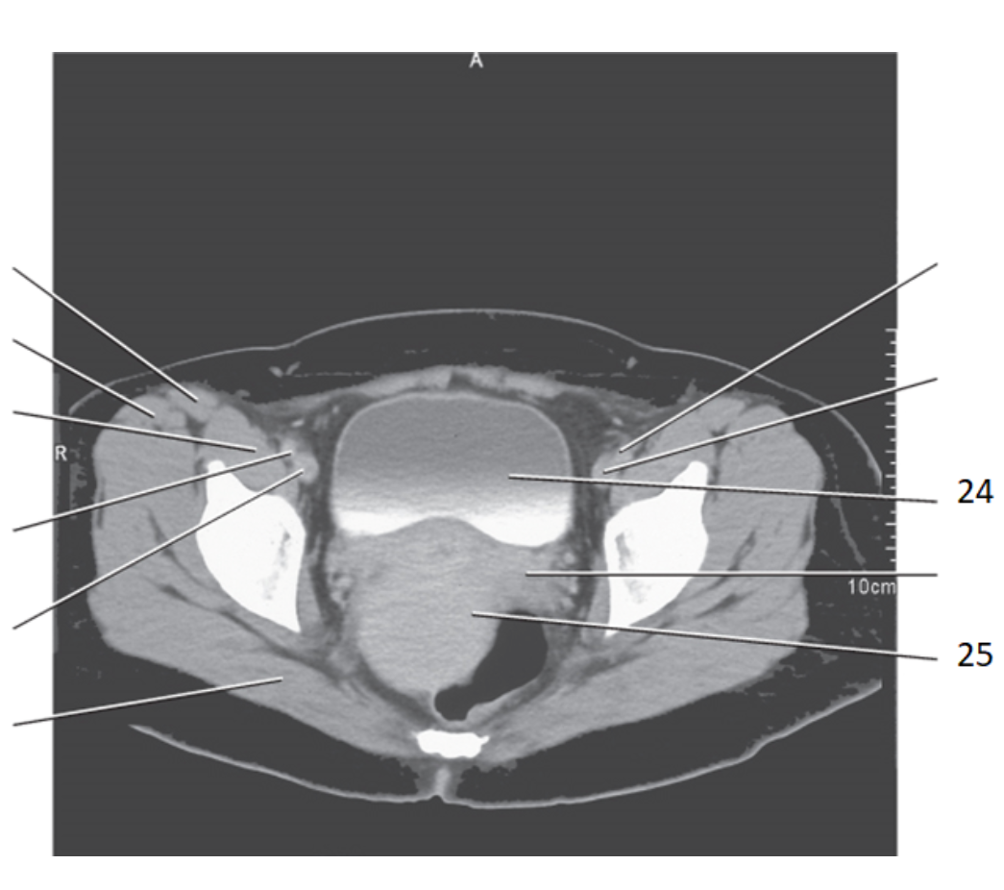

2

sacral prominatory

19

greater trochanter

17

pubic bone

20

prostate

25 women

uterus

24

aorta